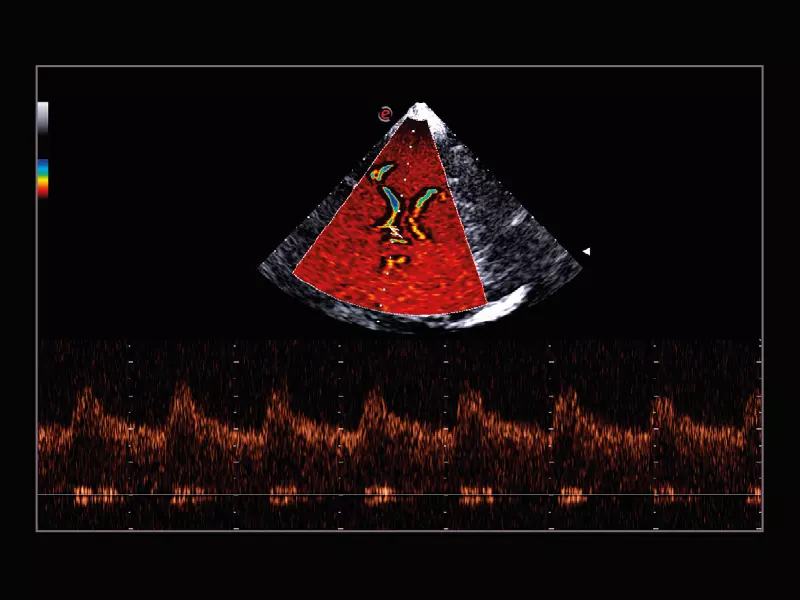

Q7 - Cardio CFM

Q7 - Cardio CFM

MyLab™X1 - Apical view CFM

MyLab™X1 - Apical view CFM

MyLab™A50 - Heart CFM

MyLab™A50 - Heart CFM

MyLab™A70 - Heart CFM

MyLab™A70 - Heart CFM